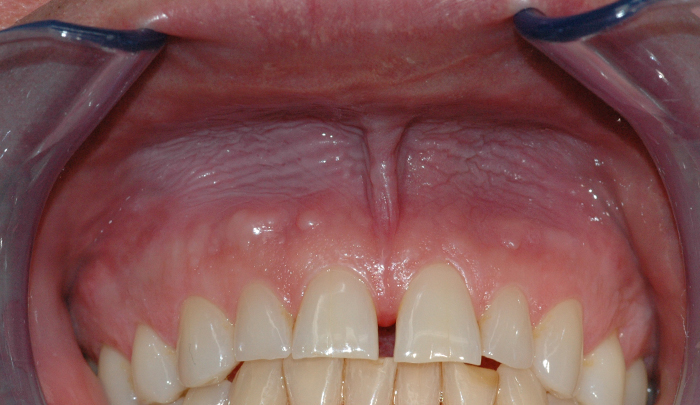

Slimhinnen der snusen ligger, reagerer ved å bli rød og irritert. Etter lengre tids fast snusing blir slimhinnen hvitlig, fortykket og rynkete. Om man slutter å snuse, vil slike forandringer normaliseres etter en tid.

Tannkjøttet kan også påvirkes av snusbruk. Man kan etter hvert se at tannkjøttet trekker seg tilbake og etterlater en blottlagt rotoverflate der snusen ligger. Selv om man slutter å snuse, vil tannkjøttet ikke komme på plass igjen. Dette er altså en permanent skade. I tillegg påvirker nikotin blodtilførselen i tannkjøttet og kan øke sjansen for at infeksjoner oppstår.

Når det gjelder tennene, vil disse kunne misfarges som følge av snusing. Både sprekkdannelser i emaljen og overgangen mellom tenner og fyllinger er steder der fargestoffer fra snusen vil kunne sette seg og bidra til et skjemmende smil.